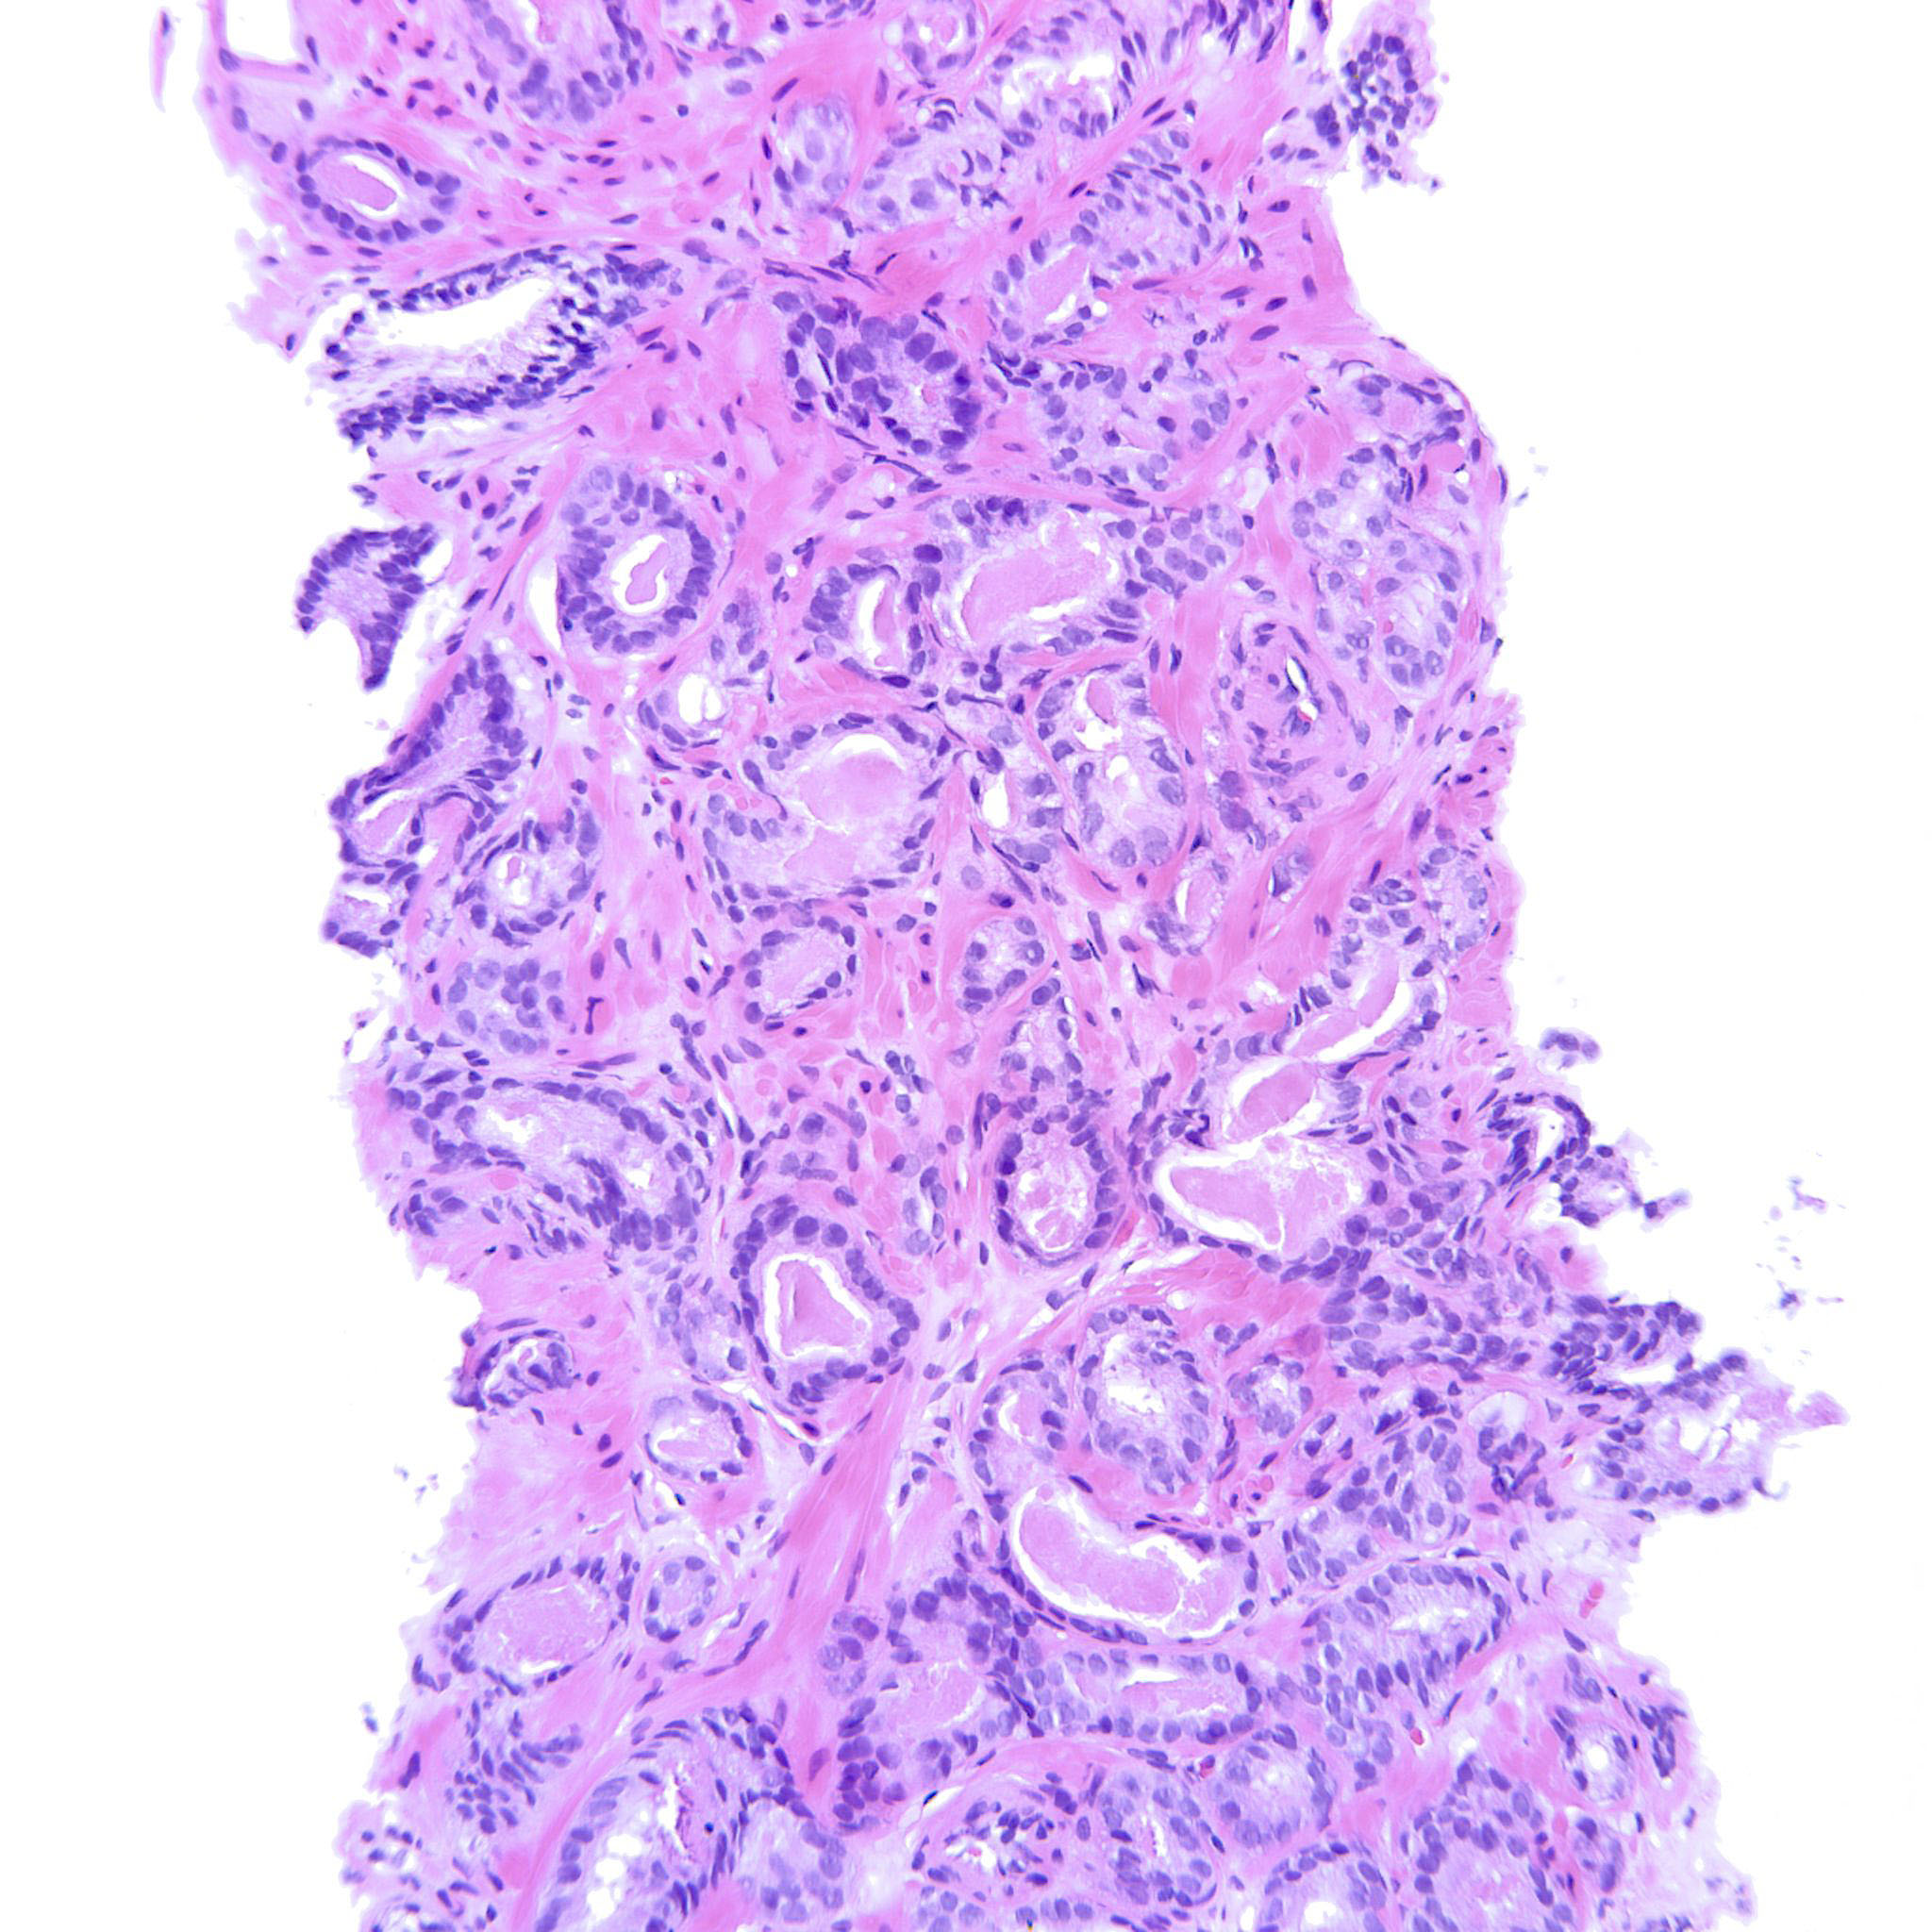

Prostate cancer grading

Case ID: 207